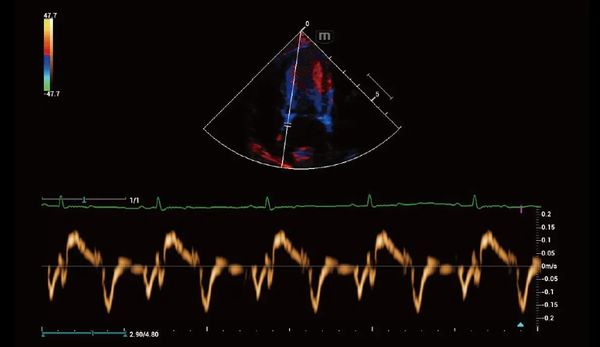

Similar al espíritu inherentemente rápido y nítido de un jaguar, Vetus 9 ofrece imágenes 10 veces más rápidas, enfoque dinámico de píxeles y tecnologías originales de recuperación de señal ecográfica, lo que permite a los veterinarios enfrentarse a todos los escenarios clínicos con facilidad.

La plataforma ZST+ es una innovación extraordinaria, que representa una evolución de la tecnología de ultrasonidos. Transforma las métricas de los ultrasonidos de la formación de haces convencional al procesamiento basado en canales. Supera la tradicional limitación de compensación entre resolución espacial, resolución temporal y uniformidad tisular, proporcionando una calidad de imagen excepcional en diversos escenarios clínicos veterinarios y ofreciendo una confianza notable.